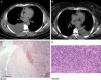

Radiological and histological features observed in the described clinical cases (Case 1: A and C, Case 2: B and D).

(A) Chest CT image demonstrating a right pleural effusion with atelectasis of the adjacent lung parenchyma and areas with pleural thickening.

(B) Chest CT image revealing a left pleural effusion with associated pulmonary atelectasis.

(C) Photomicrograph illustrating the presence of lung parenchyma with mesenchymal neoplasm in continuity, with expansive margin and heterogeneously deposition of hyaline matrix with foci of hemorrhage. Stain: hematoxylin and eosin (HE); magnification: 40×.

(D) Photomicrograph showing the presence of pleura involved by neoplasia, composed of epithelioid cells of irregular ovoid nuclei and eosinophilic cytoplasm, often with vacuoles and some erythrocytes inside. Stain: hematoxylin and eosin (HE); magnification: 200×.